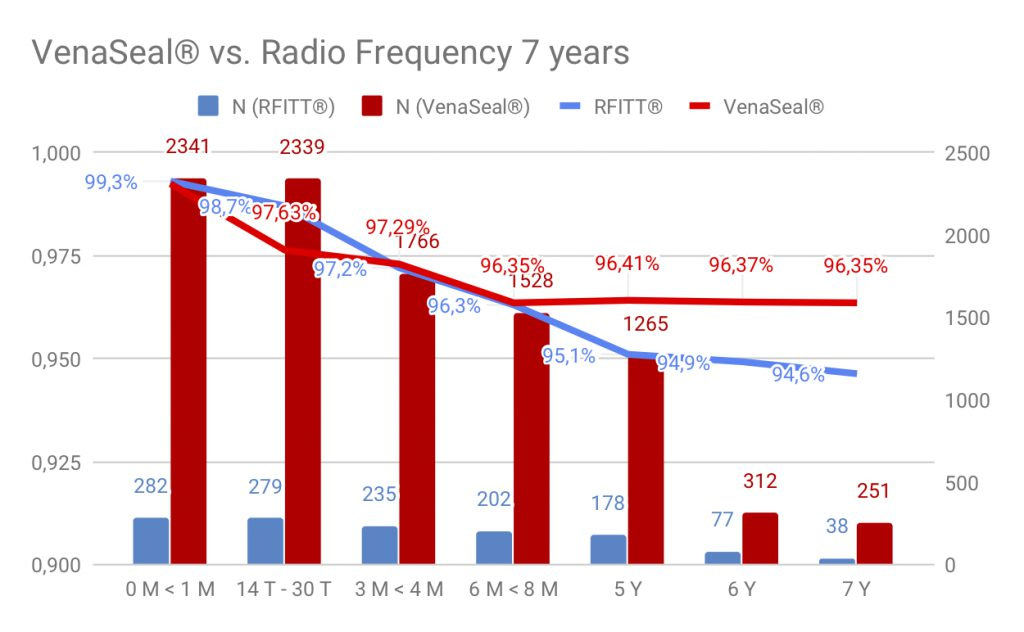

Duplex control follow up over 86 months: the first day 2464 veins were re-examined. 2448 veins were sealed initially = 99,35% closure rate.

After 14 – 30 days we found 48 partial and 12 completely recanalized veins able to follow up of 2454 sealed truncal veins (99,50%) = 97,55% closure rate.

Three to four months post operationem we had 50 partial and 20 complete recanalisations able to follow up 1873 veins (76 %) = 97,16% closure rate.

After eight to ten months we observed 59 partial and 35 complete recanalisations able to follow up 1607 veins (65,2%) = 96,19% closure rate.

No further recanalisations were found after 87 months up to now! The closure rate over all the time of 87 months = 96,19%.

Closure rate of VenaSeal® compared to radiowave / Laser is same or better. VenaSeal® works without mechanical or thermal energy, side effects of laser or radio wave are not an issue here.